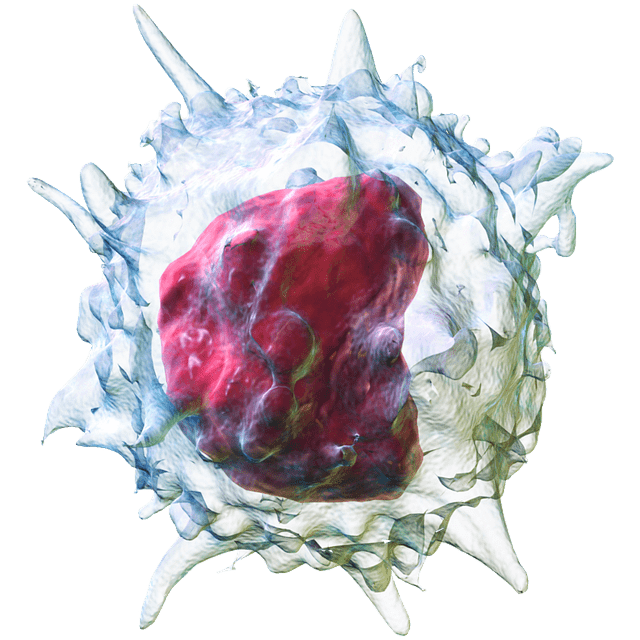

Negli ultimi anni, si è visto un numero crescente di lavori epidemiologici che dimostrano che la solitudine aumenta le probabilità di ammalarsi: sembra che induca il rilascio cronico di ormoni che mettono in crisi la funzione immunitaria. I cambiamenti biochimici dovuti alla solitudine possono accelerare la diffusione del cancro, le malattie cardiache e l’Alzheimer, o semplicemente indebolire la volontà di andare avanti. La capacità di misurare e rilevare questa condizione potrebbe aiutare a identificare le persone a rischio e aprire la strada a nuovi tipi di interventi.

Tye si è concentrata su popolazioni specifiche di neuroni nel cervello dei roditori che sembrano essere associate a un bisogno misurabile di interazione sociale, una “fame” che può essere manipolata stimolando direttamente i neuroni stessi. Per individuare questi neuroni, Tye si è basata su una tecnica che ha sviluppato mentre completava la sua specializzazione nel laboratorio dell’Università di Stanford di Karl Deisseroth.

Deisseroth è stato un pioniere dell’optogenetica – una tecnica in cui proteine geneticamente modificate e sensibili alla luce vengono impiantate nelle cellule cerebrali – che permette ai ricercatori di accendere o spegnere i singoli neuroni semplicemente illuminandoli con i cavi in fibra ottica. Sebbene la tecnica sia troppo invasiva da usare nelle persone, con cavi in fibra ottica che devono attravere il cranio per finire direttamente nel cervello, essa consente ai ricercatori di modificare i neuroni in diretta e osservare il comportamento dei roditori che si muovono liberamente.

Tye ha iniziato a utilizzare l’optogenetica nei roditori per tracciare i circuiti neurali coinvolti nelle emozioni, nella motivazione e nei comportamenti sociali. Ha scoperto che attivando un neurone e quindi identificando le altre parti del cervello che rispondevano al segnale emesso dal neurone, poteva tracciare i circuiti discreti delle cellule che lavorano insieme per svolgere funzioni specifiche. Tye ha tracciato meticolosamente le connessioni dall’amigdala, un insieme di neuroni a forma di mandorla ritenuta la sede della paura e dell’ansia sia nei roditori che negli esseri umani.